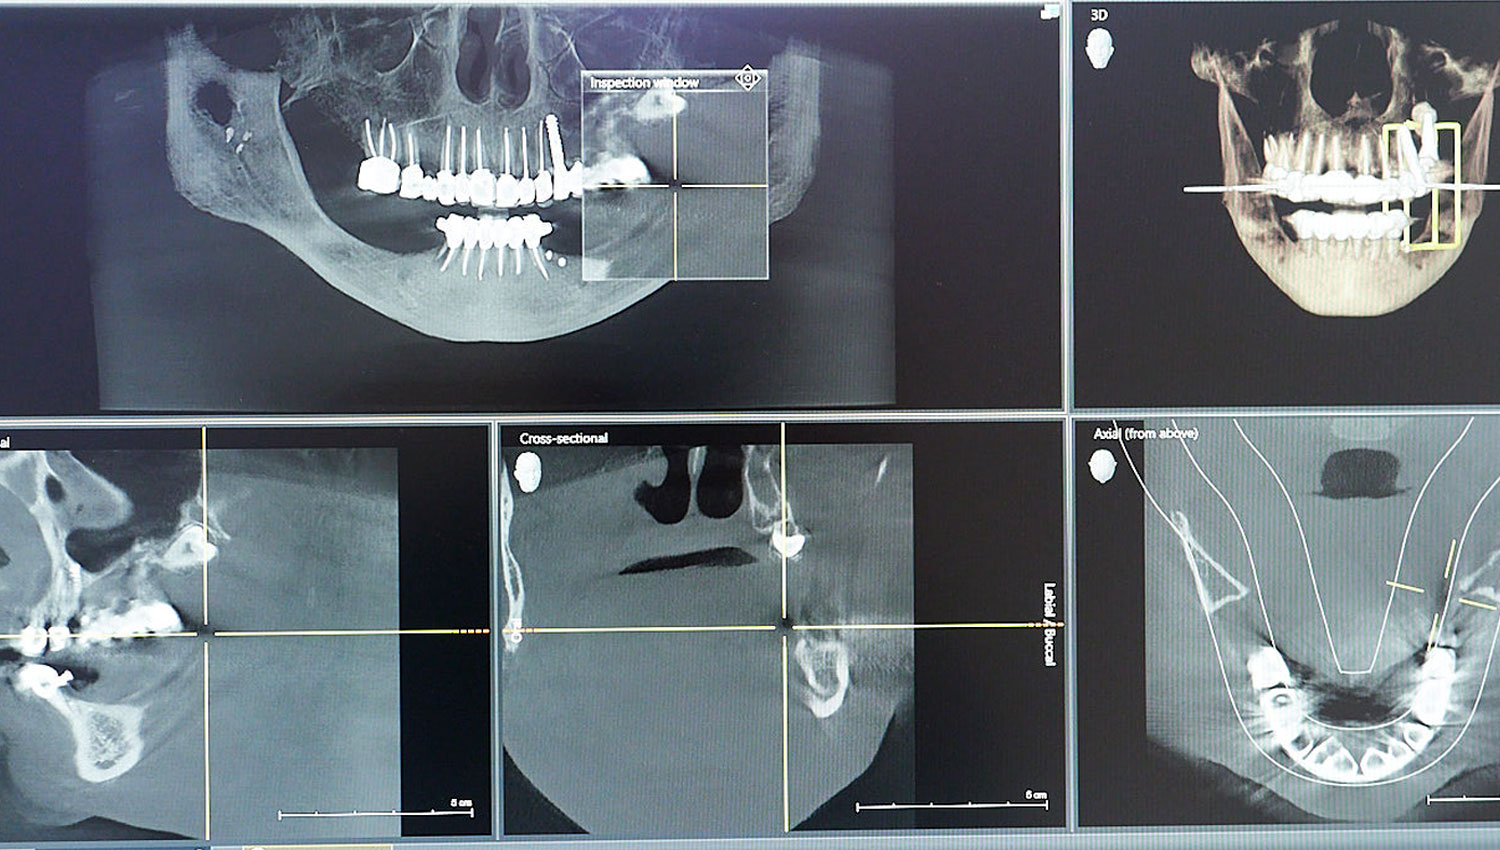

Ψηφιακος Ορθοπαντομογραφος & ΑΞΟΝΙΚΟΣ ΤΟΜΟΓΡΑΦΟΣ ΓΝΑΘΟΥ

Χρησιμοποιεί χαμηλής δόσης ακτίνες Χ για να απεικονίσει τα δόντια και τις γνάθους για τη διάγνωση παθολογίας και τον προγραμματισμό οδοντιατρικών επεμβάσεων